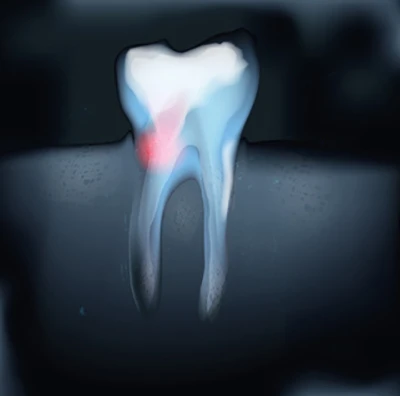

Gojenie zmian

Obraz wygojonych tkanek okołowierzchołkowych po leczeniu kanałowym pod mikroskopem.